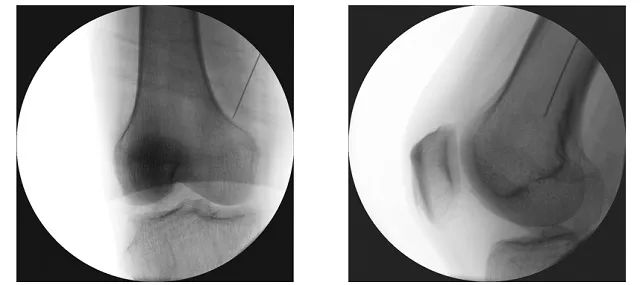

“膝关节感觉神经射频技术”就是用X线和/或超声定位支配膝关节感觉的神经,然后将射频针穿刺到这些神经周围,对神经进行射频热凝术,从而达到镇痛的目的,缓解膝关节严重骨关节炎的疼痛和功能障碍。